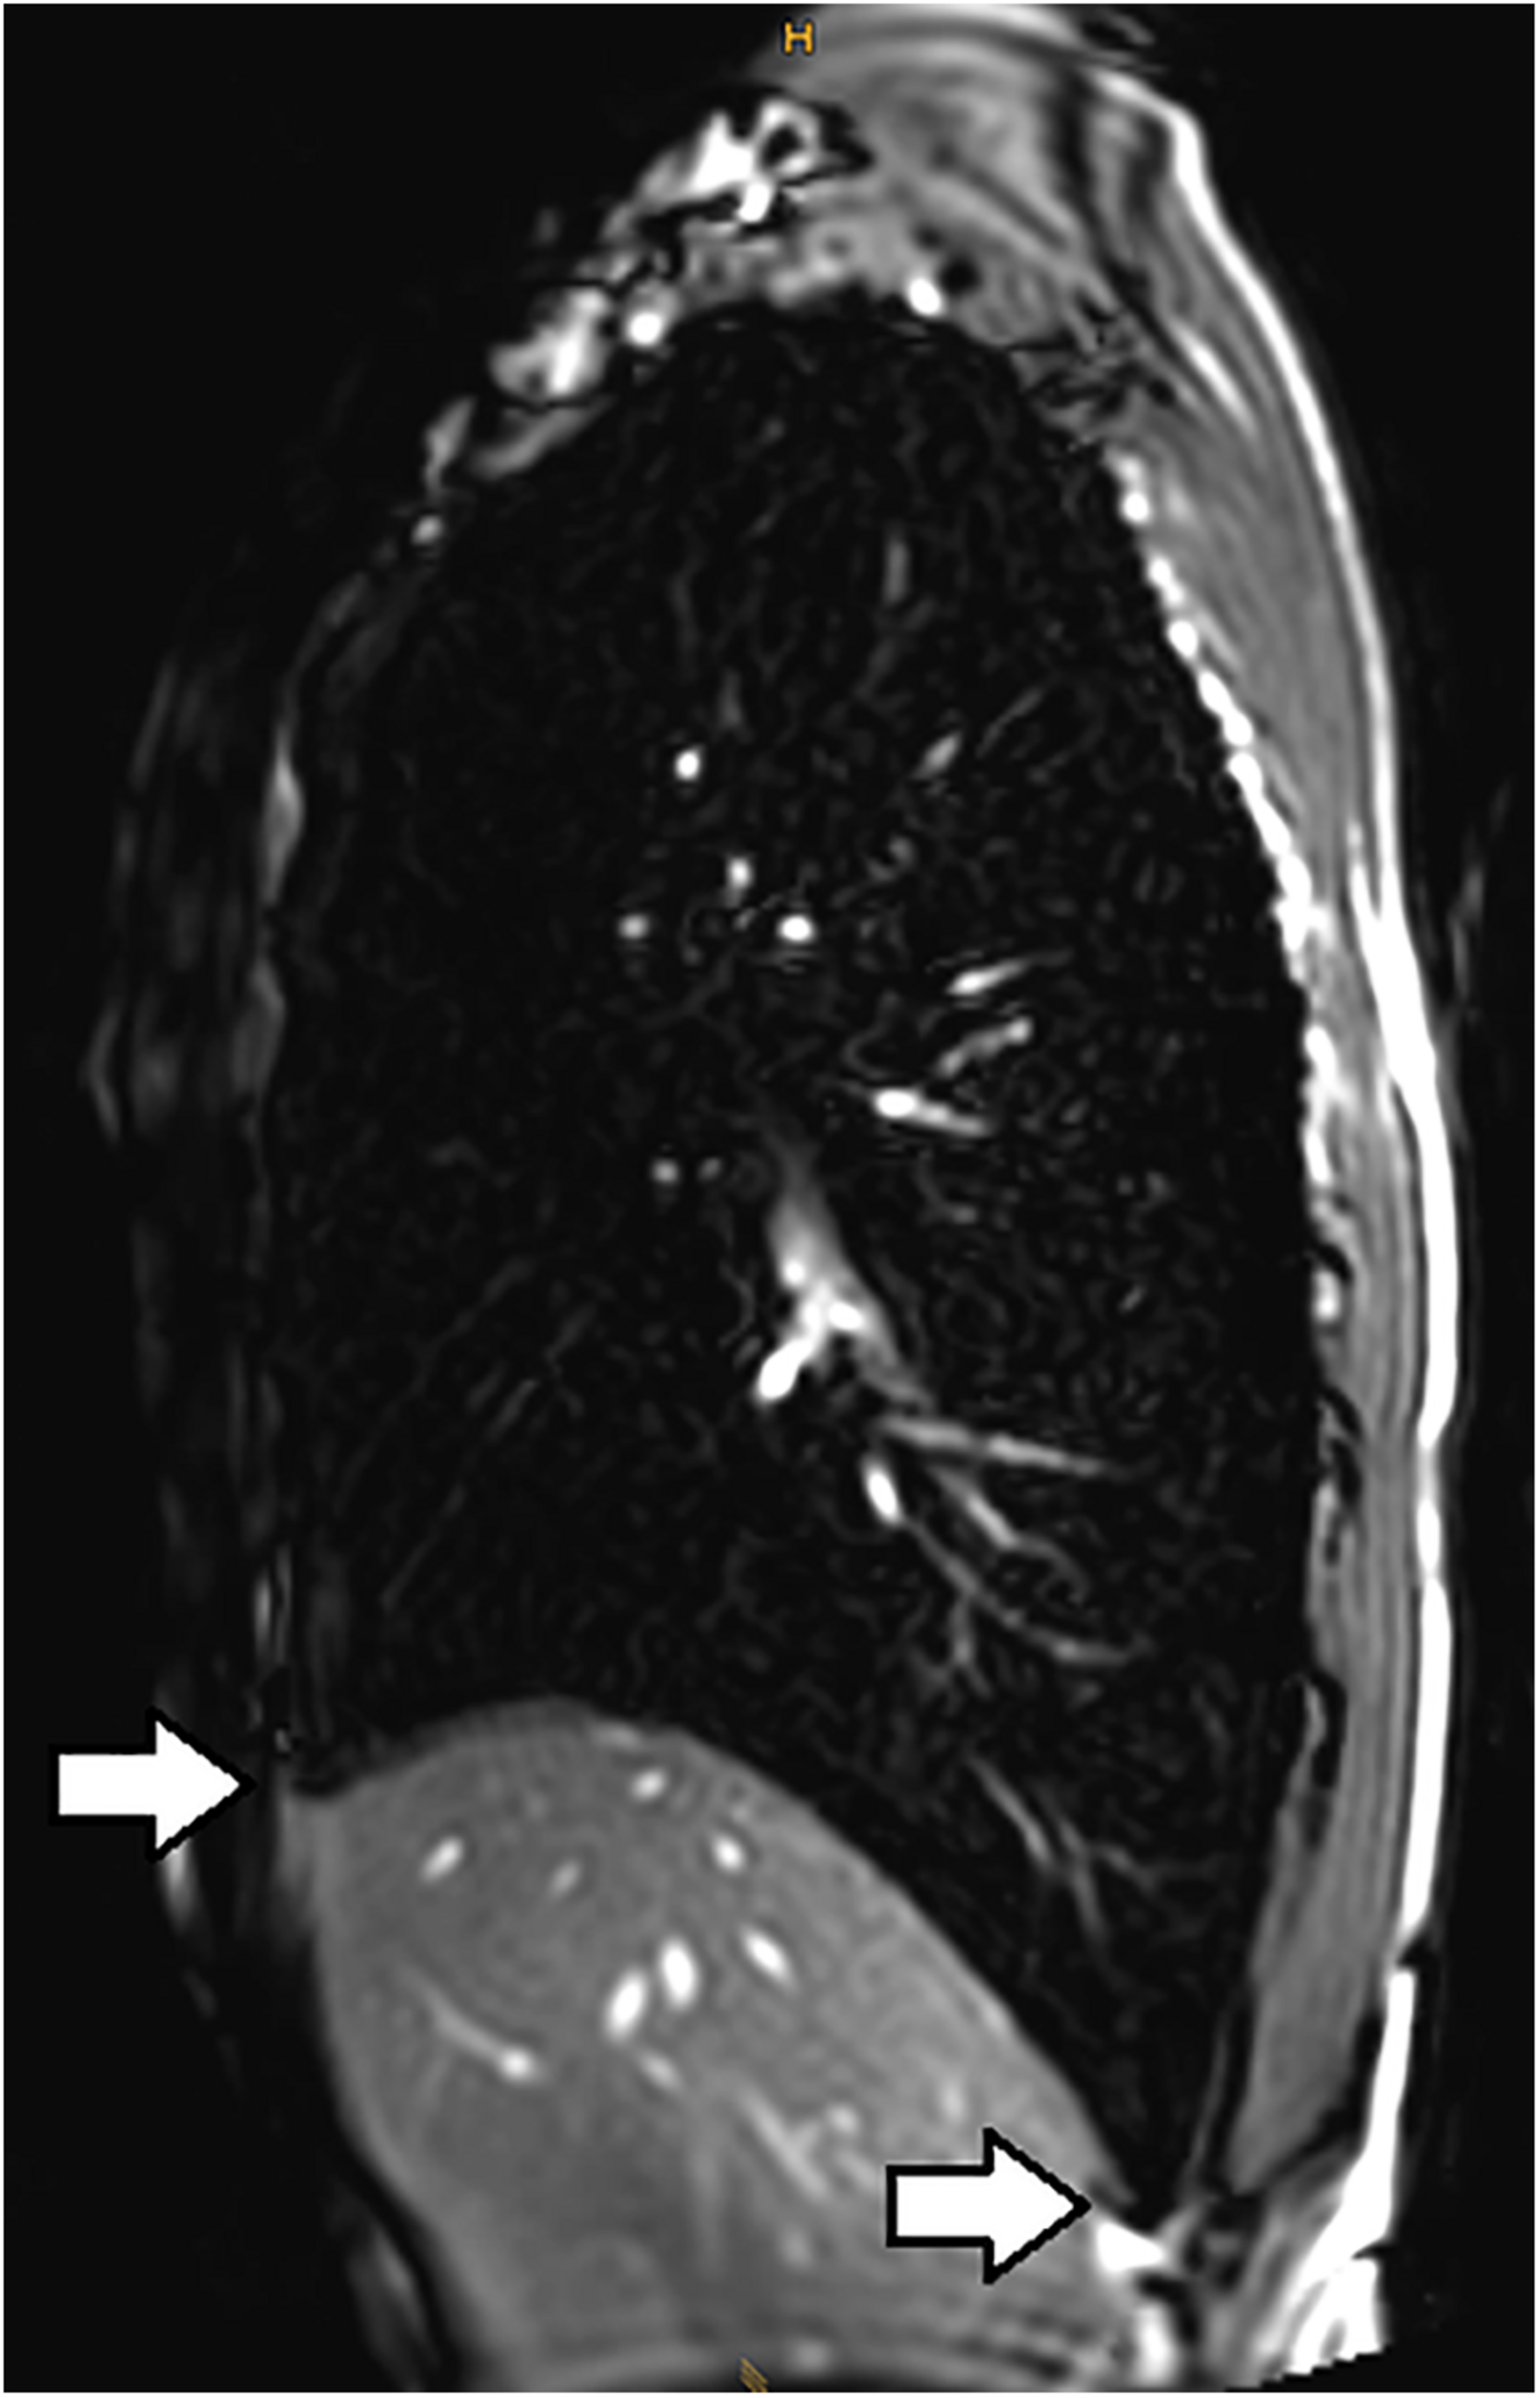

Lindhom and Nyren (2005) also investigated magnetic resonance imaging (MRI) during glossopharyngeal insufflation and described a reduction of thoracic blood volume with emptying of the vessels and heart, and a downward shift of the diaphragm. In a study employing dynamic MRI and spirometry, Eichinger et al. (2008) demonstrated that the shape of the thorax was primarily preserved despite the marked increase in total lung volume as measured by MR-spirometry. Herniation of the lung underneath the sternum and enlargement of the costodiaphragmatic angle furthermore demonstrated the distensibility and high performance of trained lungs (see Figure 1). Seccombe et al. (2010) measured single photon emission computed tomography (CT) of the chest after labeled albumin injection and showed markedly diminished or even absent lung perfusion in areas of expanded lung. Lung hyperinflation induced by glossopharyngeal insufflation elicits significant hemodynamic effects, including a decrease in systemic arterial blood pressure as well as decrease in cardiac output (Potkin et al., 2007). Hypotension with glossopharyngeal breathing is associated with acute biventricular systolic dysfunction (see Figure 2, video axial sequence 113–293). Cardiac MRI revealed changes resembling pulmonary arterial hypertension which however were reversible shortly after cessation of voluntary lung hyperinflation (Eichinger et al., 2010). Quantitative analyses of pulmonary and central blood volume changes revealed an almost 50% decrease of central blood volume after lung hyperinflation in the non-immersed state (Mijacika et al., 2017a), and it could be shown that this lung hyperinflation results in translocation of blood from the central blood volume into abdominal, pelvic, and peripheral veins (Mijacika et al., 2017b).

Figure 1. Subxiphoidal and costodiaphragmatic recessus (marked with white arrows) filled with air during glossopharyngeal insufflation.